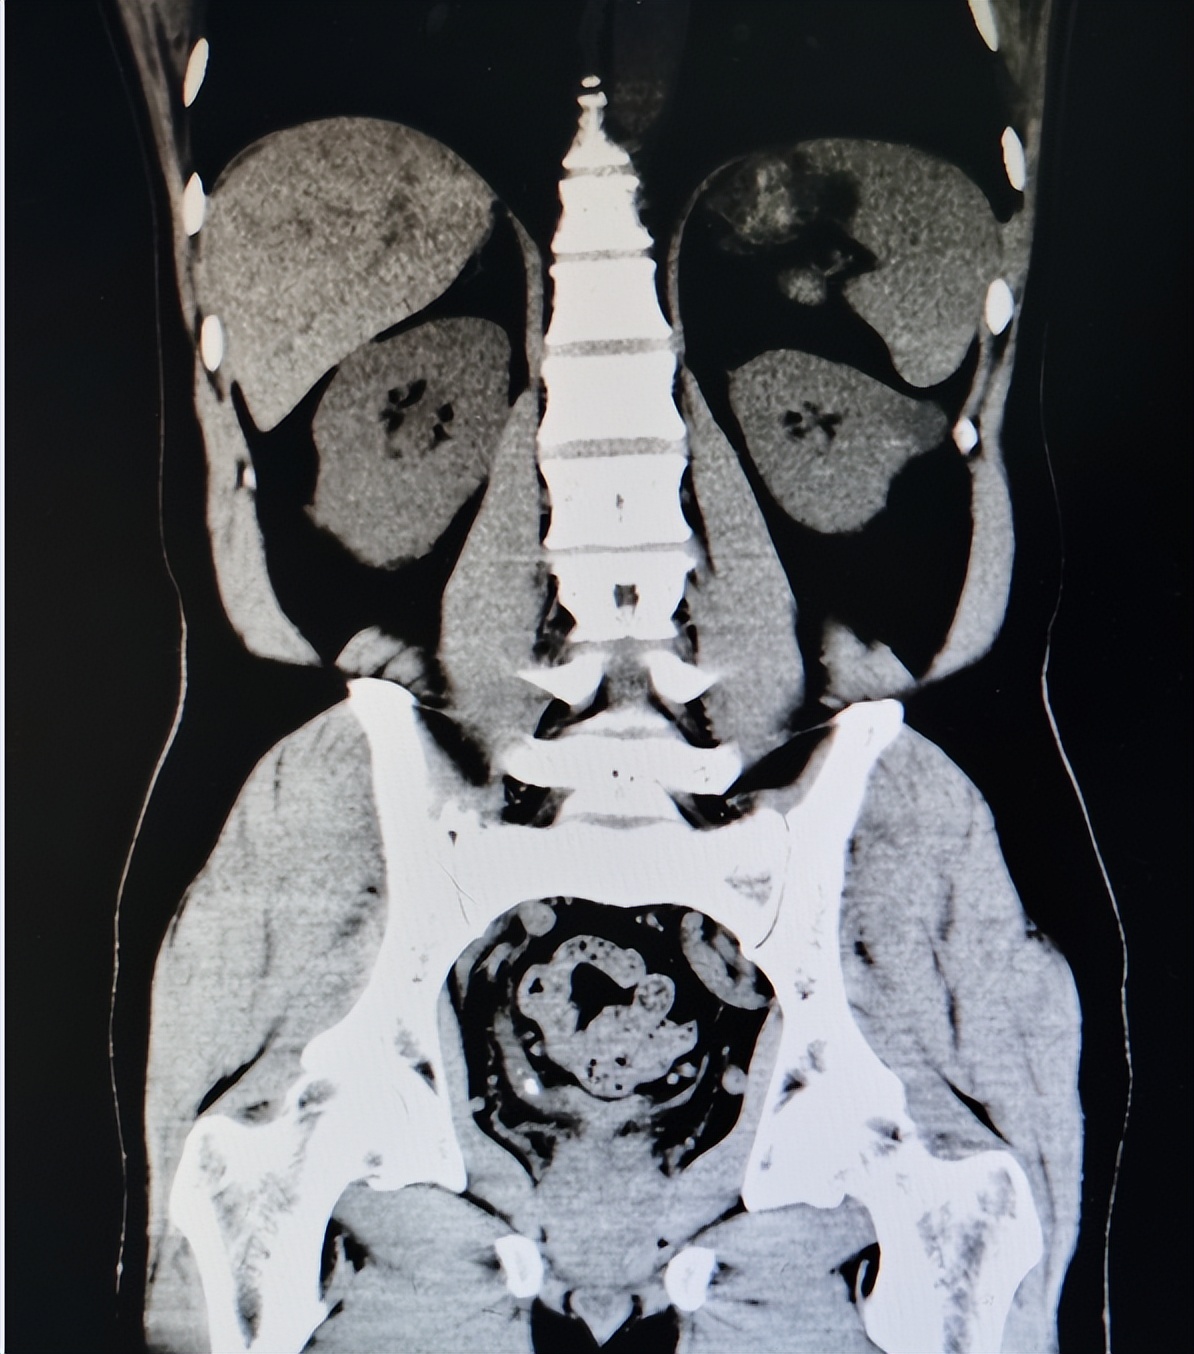

入院后,除了对患者进行专科查体外,还完善了血尿常规、CT等相关检查。其中查体提示双侧腰部未见异常隆起及包块,双侧肾区无叩痛,尿道口无红肿,无分泌物。血常规提示白细胞升高,红细胞、血红蛋白正常,尿常规提示红细胞+,CT提示右侧输尿管下段结石伴积水,结石直径为4-5cm,右肾轻度结石。

虽然患者输尿管走行区无叩痛,存在尿路感染,但结合CT等检查结果,考虑输尿管结石是引起尿路症状的主要原因,而非尿路感染。因此,最终确定诊断为右侧输尿管结石。因为患者结石较大,患病周期较长,对患者产生了严重影响,因此考虑行输尿管镜下激光碎石。